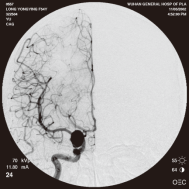

右侧颈内动脉后交通动脉瘤栓塞术前 左椎动脉造影 示左椎动脉夹层动脉瘤: 左椎动脉发出小脑后下动脉处呈囊性扩张,动脉瘤远端血管狭窄

弹簧圈栓塞后造影示左椎动脉夹层动脉瘤消失, 左椎动脉、 多发动脉瘤夹闭术前、术中

左侧小脑后下动脉循环通畅